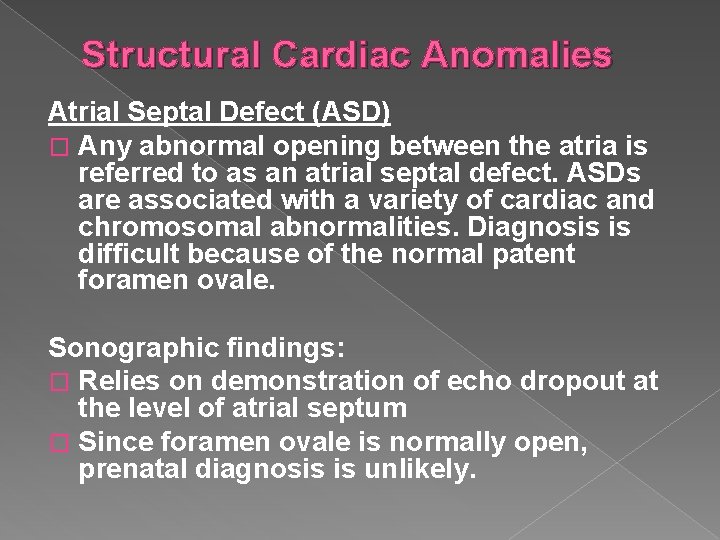

Structural Cardiac Anomalies Atrial Septal Defect (ASD) � Any abnormal opening between the atria is referred to as an atrial septal defect. ASDs are associated with a variety of cardiac and chromosomal abnormalities. Diagnosis is difficult because of the normal patent foramen ovale. Sonographic findings: � Relies on demonstration of echo dropout at the level of atrial septum � Since foramen ovale is normally open, prenatal diagnosis is unlikely.

ASD- Atrial septal defect Any abnormal opening between the atria is an ASD. Hard to diagnosis because of the normal patent foramen ovale.